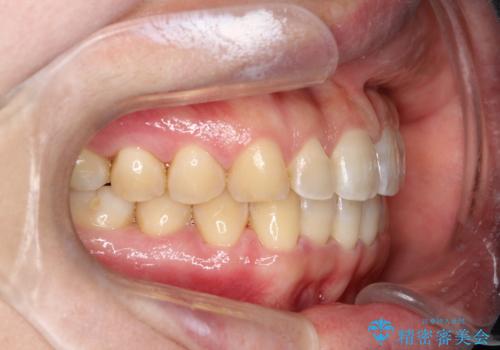

【インビザライン】前歯のすきまを閉じたい

- 前歯の隙間を主訴に来院されました。

インビザライン にて治療を行い、歯並びを改善することができました。